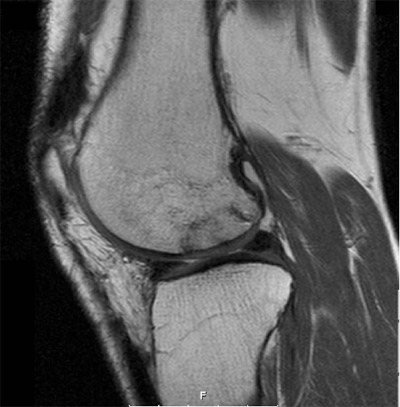

The indications for the index procedure in this series were Outerbridge grade IV osteochondral lesions [10], large osteochondrosis dissecans with nonvital or loose fragments (A/B International Cartilage Research Society osteochondrosis dissecans grade III and IV) [11], and focal osteonecrosis in the weight-bearing zone of the femoral condyle larger than approximately 4 cm2 or osteochondral lesions that could not be addressed by standard osteochondral transfer techniques for other reasons (for example, depth) (Figure 1).

Figure 1. Preoperative magnetic resonance imaging scan of a deep osteochondral lesion. The left image shows the lesion in a sagittal view, eliciting the cartilage damage and the subchondral sclerosis. The right image shows shows the extension of the bone defect in a coronal image.